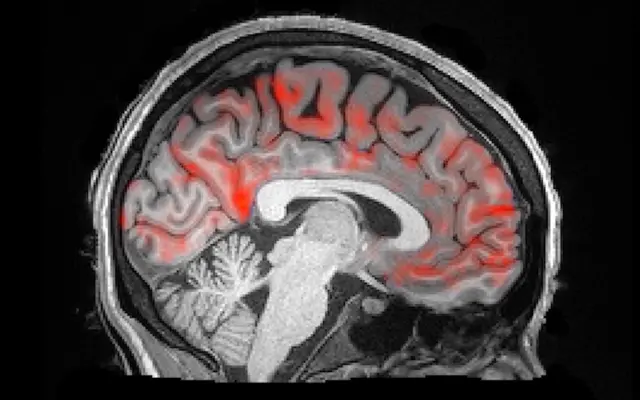

En el estudio, los científicos analizaron una extensa colección de más de 10.000 imágenes de resonancia magnética funcional (fMRI) de personas en estado de reposo y durante la realización de tareas específicas.

Mediante la reconstrucción de estos escaneos, se crearon mapas cerebrales individuales para cada participante. Los resultados revelaron una conexión entre la función cerebral y la geometría del cerebro, lo que sugiere que la estructura morfológica del cerebro desempeña un papel importante en su funcionamiento.

Estos descubrimientos podrían facilitar la predicción de patrones de actividad cerebral durante estados de enfermedad mediante la simple observación de la geometría de este órgano. Por ende, se podrían tener mejores diagnósticos, así como tratamientos para los trastornos cerebrales.